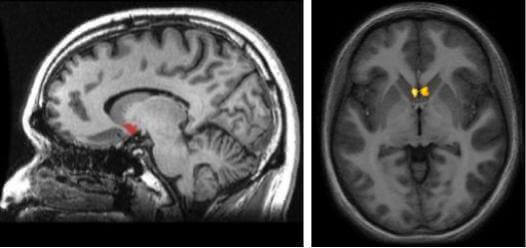

Se vi state chiedendo dove si trova questa struttura, visualizzate la zona subcorticale (al di sotto della corteccia) proprio nel punto di intersezione tra il nucleo caudato, il putamen e il setto. Uno degli aspetti più interessanti riguardo al nucleus acumbens e la sua posizione è che fa parte del percorso dopaminergico nel cervello. Si tratta del cosiddetto percorso mesolimbico, che ha il compito di inviarci degli stimoli ogni volta che il cervello comprende che stiamo facendo esperienze positive e gratificanti.

Ogni emisfero cerebrale ha il suo nucleus accumbens. In questo modo, il sistema di ricompensa gestito dalla dopamina arriva ad ogni area cerebrale. Si tratta inoltre di una struttura che fa parte dei cosiddetti gangli della base. Anche se a primo impatto e attraverso le immagini ci può sembrare molto più piccolo, i nucleus accumbens presenta un’enorme rete di connessioni.